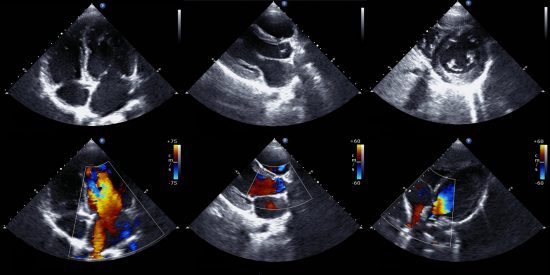

Source: 123sonography.com

There are many ways that sound waves can help make a diagnosis, like when an echocardiogram’s images reveal an unhealthy heart. To help you make a decision, we have outlined the main differences between diagnostic medical sonography and cardiac sonography. Many of you believe that i am just an echo student, however, i actually study echo and vascular. Cardiovascular sonography is a specialty within the collective of diagnostic medical sonography. Cardiac vs. Medical Sonographer What Are The Differences?.

The ultrasound procedure is performed to track the baby’s growth and health. Medical sonography, it's clear that the educational requirements and job duties are nearly identical. Different career paths and salaries. Cardiac ultrasound is just directed at the structures of the heart. Echo vs VascularUltrasoundSonographyStudent YouTube.

Echocardiography and vascular ultrasound are 2 distinct modalities that a sonographer can become registered in. In 2018, we introduced basic general. Obstetrics and gynecology sonographers mainly work in imaging the female reproductive system. Vascular sonography is a challenging yet rewarding profession. The Normal Fetal and Newborn Heart Fetal Newborn Pediatric nursing.